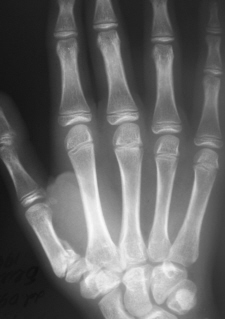

ИзображениеИзображениеИзображение